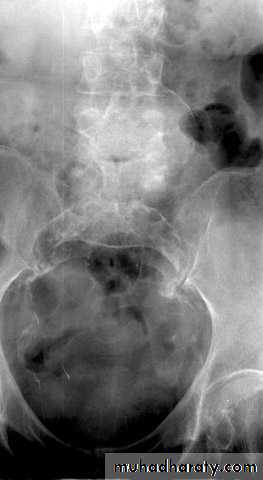

Plain Abdominal X-ray